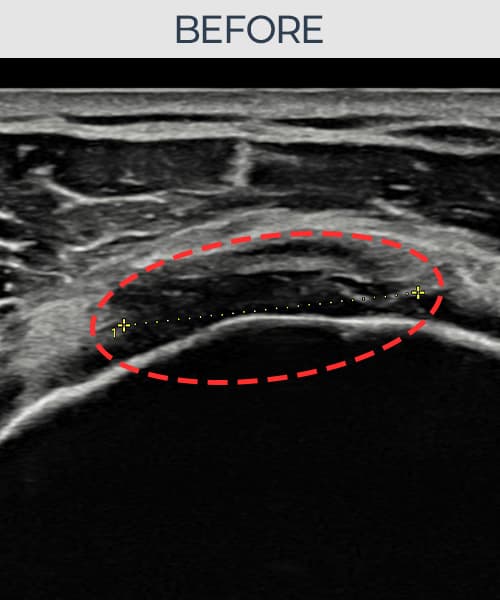

超声确认旋转肌腱袖 关节面侧部分撕裂(8mm × 5mm (肌腱厚度约45%缺损))。缩小缝合术后肌腱连续性恢复,患者回归正常生活。

术前

术前超声确认旋转肌腱袖 关节面侧部分撕裂,冈上肌腱回声不连续伴肌腱缺损(8mm × 5mm (肌腱厚度约45%缺损))。术后超声显示撕裂部位充满再生组织,肌腱连续性恢复,回声模式正常化。

该患者持续肩痛。详细超声检查确认旋转肌腱袖 关节面侧部分撕裂(缺损:8mm × 5mm (肌腱厚度约45%缺损))。在超声引导下实施非手术缩小缝合术。术后佩戴支具约4-6周,随后进行分阶段康复锻炼。随访超声确认肌腱连续性恢复、结构稳定,患者顺利回归日常生活。